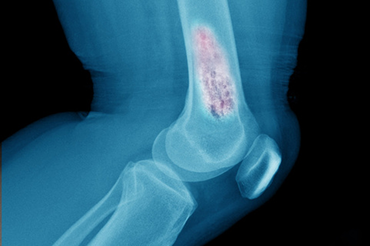

Bone Cancer Types, Screening, and Prevention